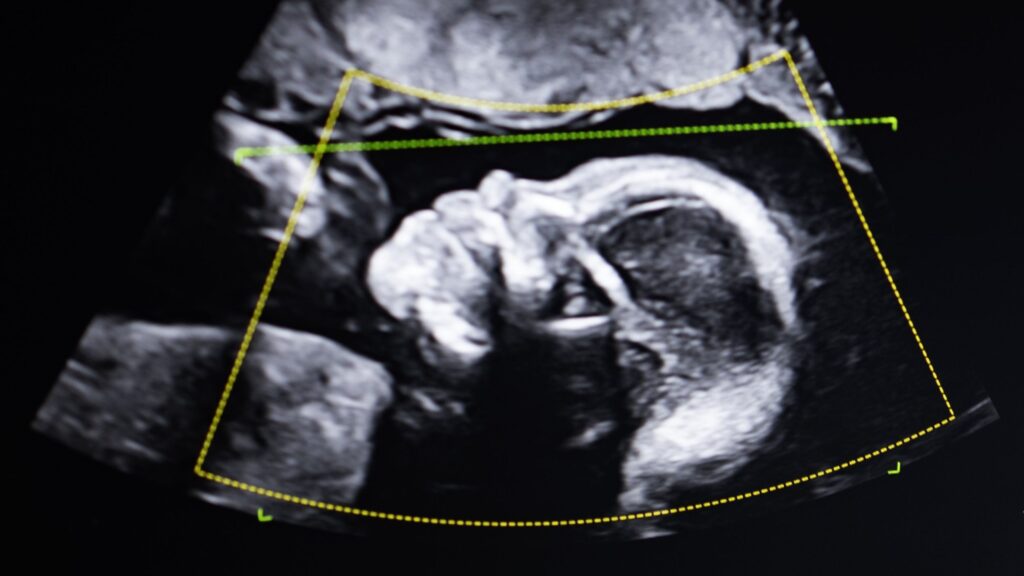

Fairchild was pregnant with her third child at the time, and the judge required that both mother and baby be tested immediately after birth. Then the unthinkable happened. The third child who had just emerged from Fairchild’s womb was also not her son, genetically speaking.